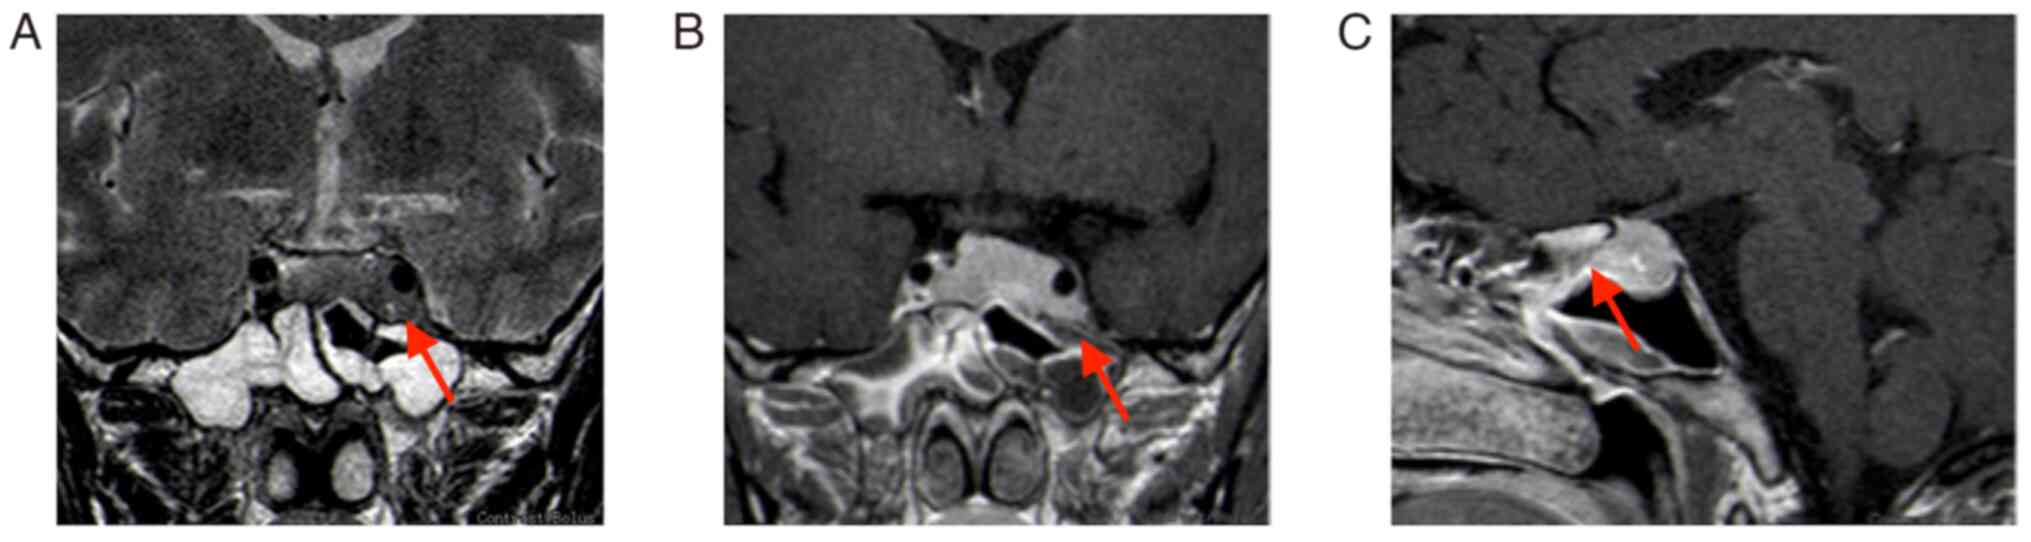

The second MRI (January 2022) performed at the hospital of the present study (the Affiliated Suzhou Hospital of Nanjing Medical University, Suzhou, China) indicated that the tumor grew and was significantly enlarged; it invaded bilateral cavernous sinuses (size, 30×20×18 mm; Fig. 2). Following a thorough evaluation of the patient's condition, a transnasal endoscopic saddle area tumor resection was performed at the hospital of the present study and the tumor was successfully removed. During the operation, the right part of the tumor was soft and could be removed by suction following spatula release; however, the left part was firm and could not be removed by suction; therefore, the tumor was slowly shattered with a curette and removed with tumor removal forceps. The tumor invaded the left cavernous sinus, which was considered to be its origin; bleeding was apparent when the tumor was scraped. Postoperative MRI indicated an extracted cavity with lack of enhancement over the original tumor location, suggesting satisfactory tumor clearance (Fig. 3).

Figure 2.

Review MRI 3 months after the first surgery (January 2022). (A) T2-weighted MRI; (B) enhanced T1-weighted coronal image; lesion size, 30×20×18 mm (red arrows indicate lesion areas); (C) enhanced T1-weighted sagittal image. Red arrows indicate lesion areas.